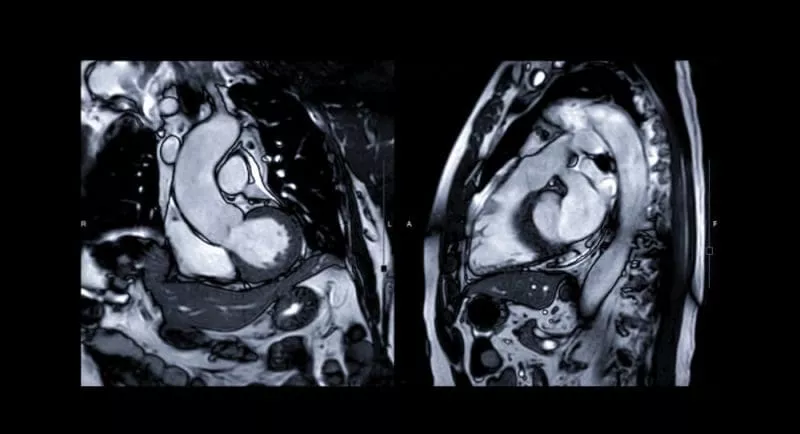

A cardiac MRI uses powerful magnets and radio waves to create detailed, moving images of your heart. During the scan, you’ll lie comfortably on a padded table while the MRI system captures precise pictures of your heart as it beats. In some cases, a contrast agent may be used to enhance certain images, but most exams require no injections. The scan is completely non-invasive and typically takes 30 to 60 minutes.

Your doctor uses these high-resolution images to assess how well your heart is pumping, evaluate blood flow, and detect conditions such as scarring, inflammation, or congenital heart defects. The results help guide early diagnosis, treatment decisions, and ongoing care. Throughout the exam, you’ll be in constant communication with your technologist to ensure your comfort and peace of mind.

Cardiac MRI provides unmatched insight into how your heart looks and works—helping doctors detect disease earlier, plan treatment with precision, and monitor recovery over time.

With Cardiac MRI, we get a complete 3-dimensional, moving picture of the heart, which can accurately measure how it functions, and spot subtle problems that other tests may miss. This allows us to guide treatment earlier and give patients greater confidence in their heart health.